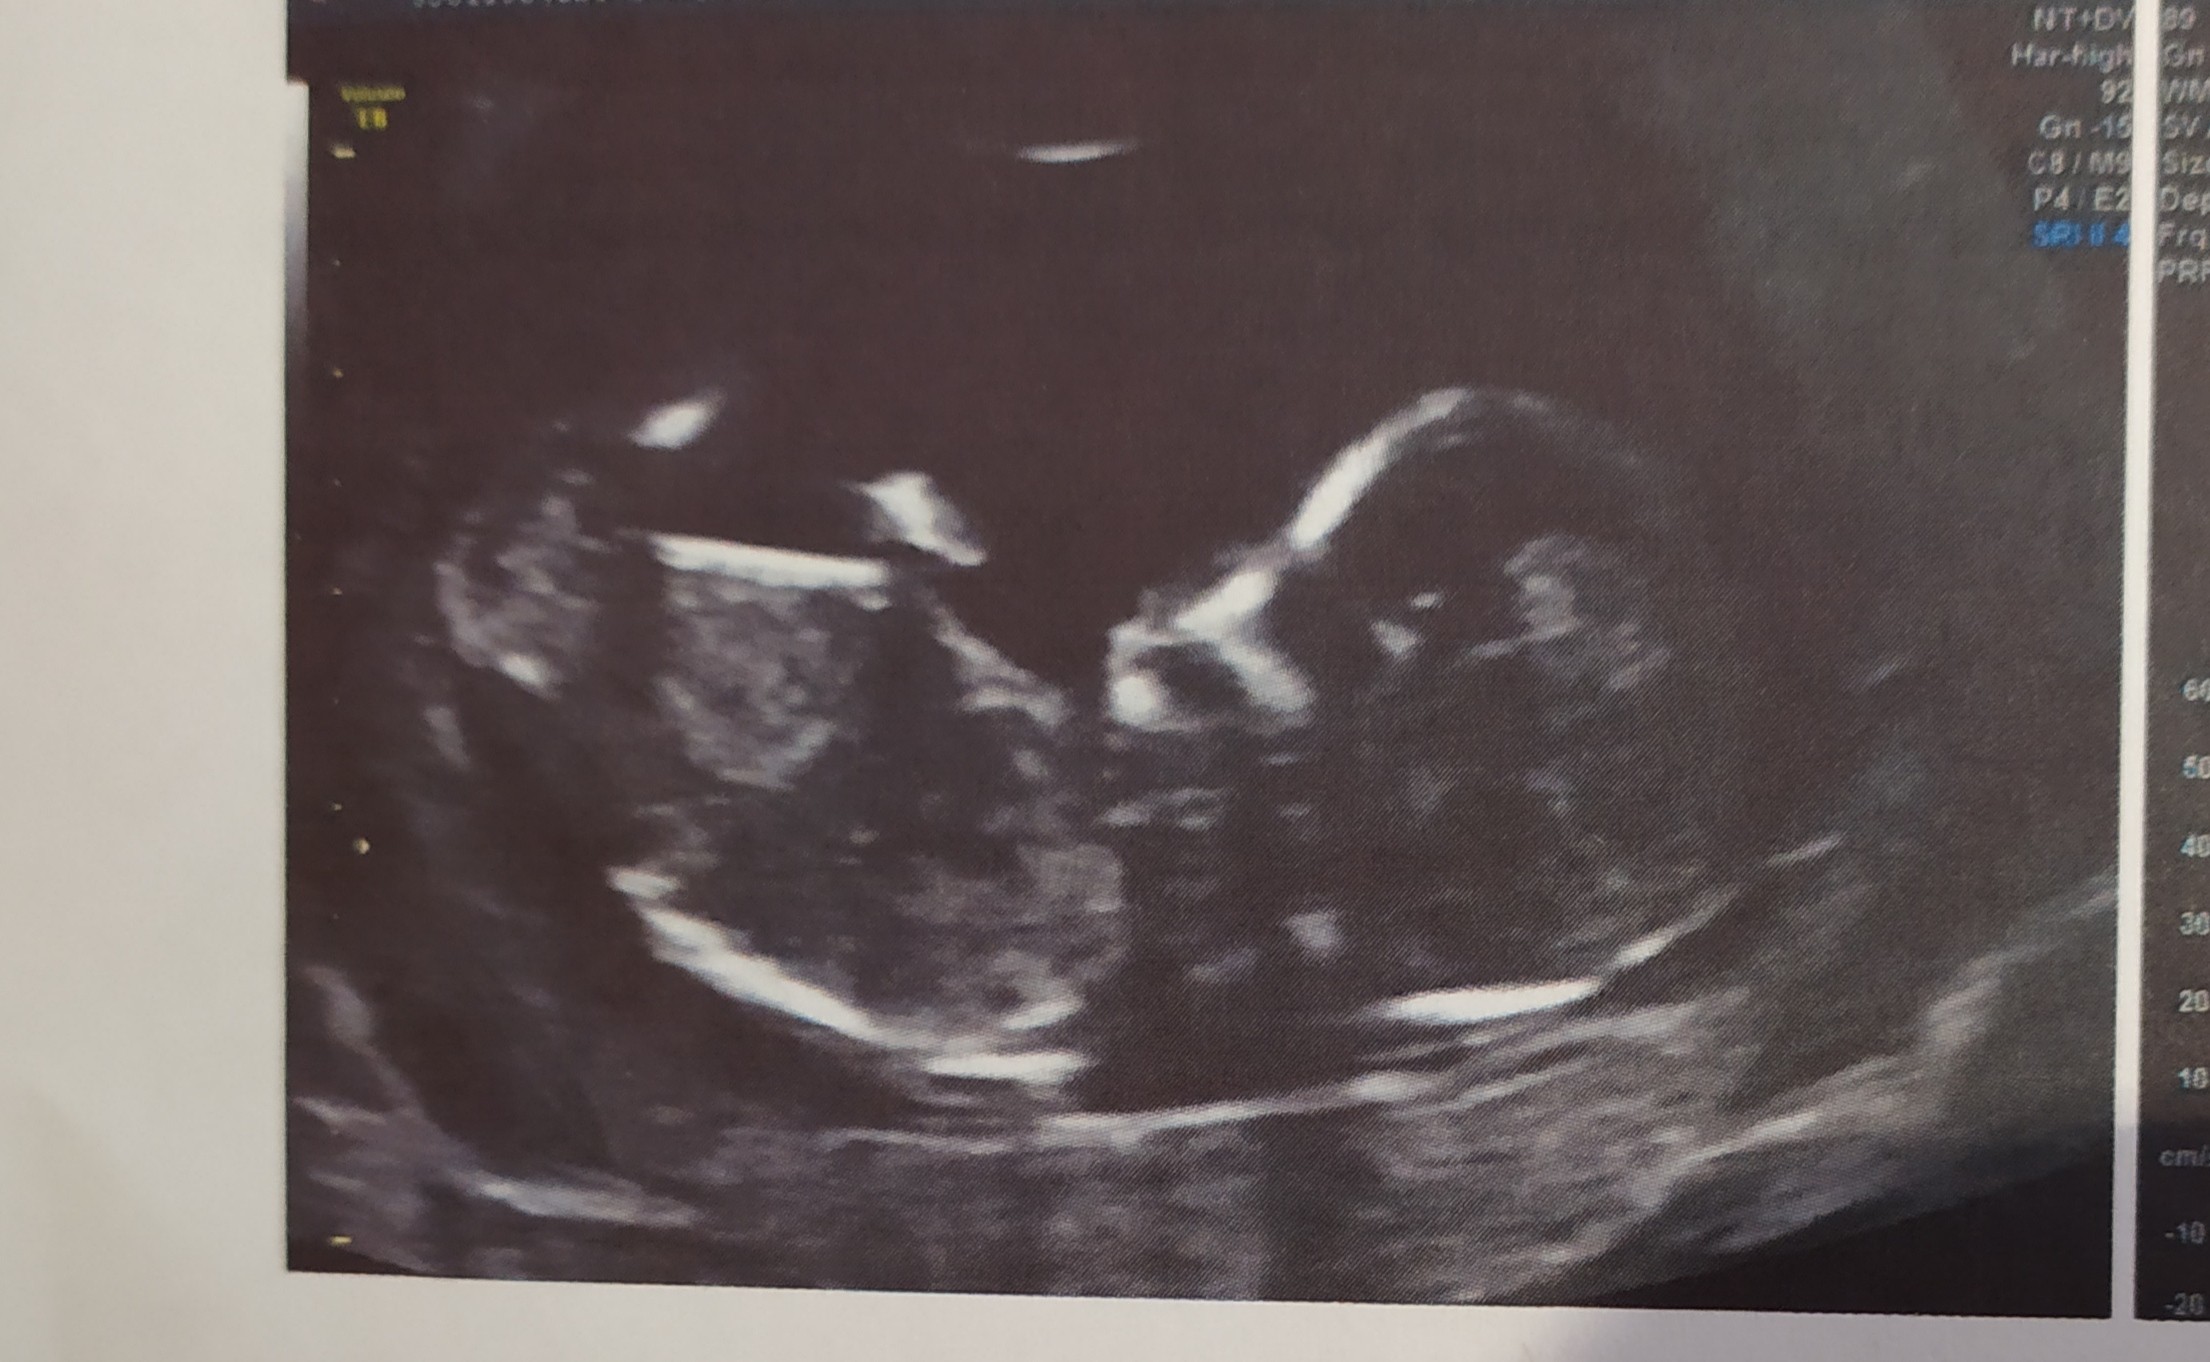

Jestem już 😁 także tak: usg wszystko oki, termin przesunął się z 11 na 7 kwietnia, według om 12+2, według usg 12+5. 6,29 cm 😍 serce 156 min. Kosc nosowa widoczna,, NT- 1.89 mm. Ale nie powiedział kto tam mieszka 😇. Kogo obstawiacie? 🤔😉

Ja myślę, że to chłopiec, chociaż po zdjęciu ciężko ocenić, bo nie widać wyrostka płciowego, a po tym podobno lekarze określają płeć dziecka we wczesnym etapie ciąży 😊 jak jest skierowany do góry to chłopak, a jak jest równolegle do ciała to dziewczynka, nawet mamaginekolog kiedyś o tym pisała 😉

Hej dziewczyny ja po, prenatalnych :) dzidziuś ma 7cm z OM 6.04 ale z USG 5.04. Ale masakra musiałam, wyjść gabinetu iść zjeść coś słodkiego II napełnić pęcherz i wrócić bo, maluch się obrócić niechcial, płci nie powiedział. NT 1,7mm wszystko prawidłowo, nosek jest :) wyniki z krwi 1:19035 . Kolejne badania prenatalne 30.11 to będzie 22tc